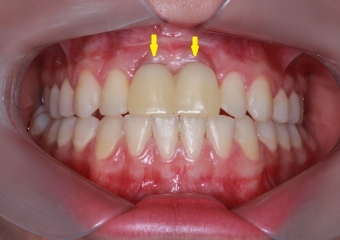

Imagem após enxerto ósseo